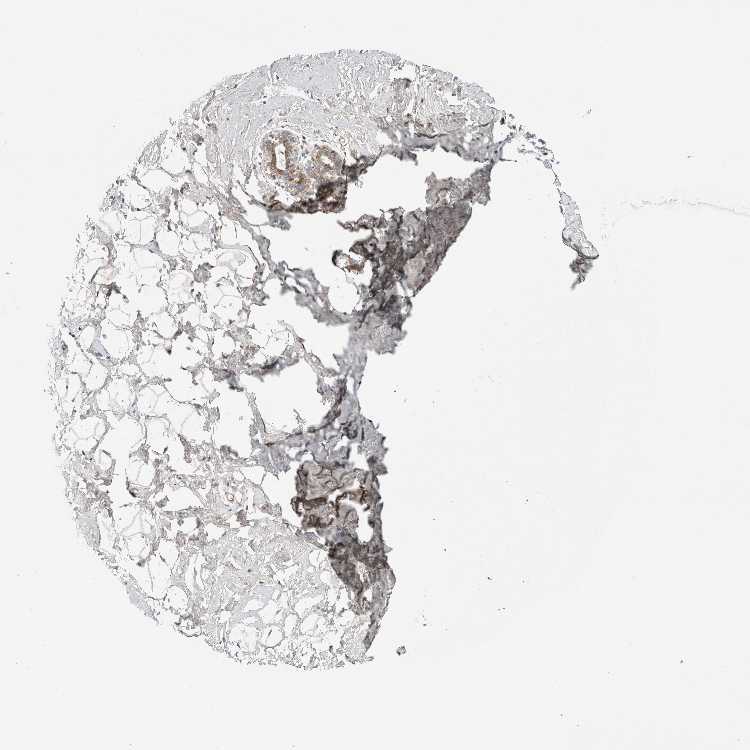

TISSUE PRIMARY DATA BREAST Show tissue menu

BREAST - Antibody stainingi

Antibody staining in the annotated cell types in the current human tissue is reported as not detected, low, medium, or high, based on conventional immunohistochemistry profiling in selected tissues. This score is based on the combination of the staining intensity and fraction of stained cells.

Each image is clickable and will lead to virtual microscopy that enables deeper exploration of all samples and also displays staining intensity scores, fraction scores and subcellular localization as well as patient and tissue information for each sample.

Antibody HPA021777Antibody HPA025306

Adipocytes Not detectedNot detected

Glandular cells Not detectedLow

Myoepithelial cells Not detectedNot detected